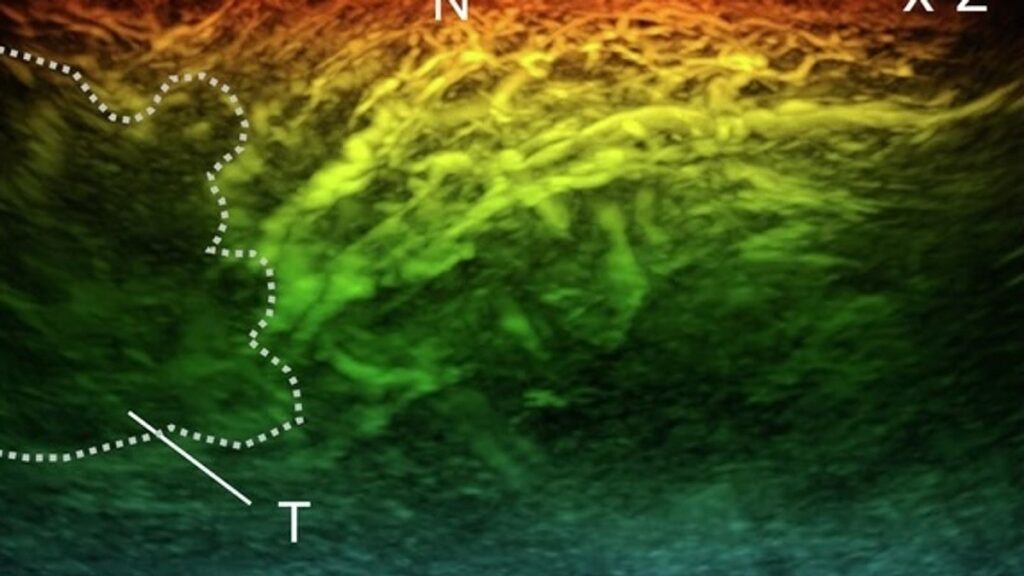

Zbulim madhor për tumoret e gjirit që janë shumë të vegjël për t’u parë në skanime

Studiuesit thonë se më në fund kanë zbuluar shkakun pse zgjat Covid – dhe lidhjen e tij e gripit me dementien

Studiuesit thonë se më në fund kanë zbuluar shkakun pse zgjat Covid – dhe lidhjen e tij e gripit me dementien